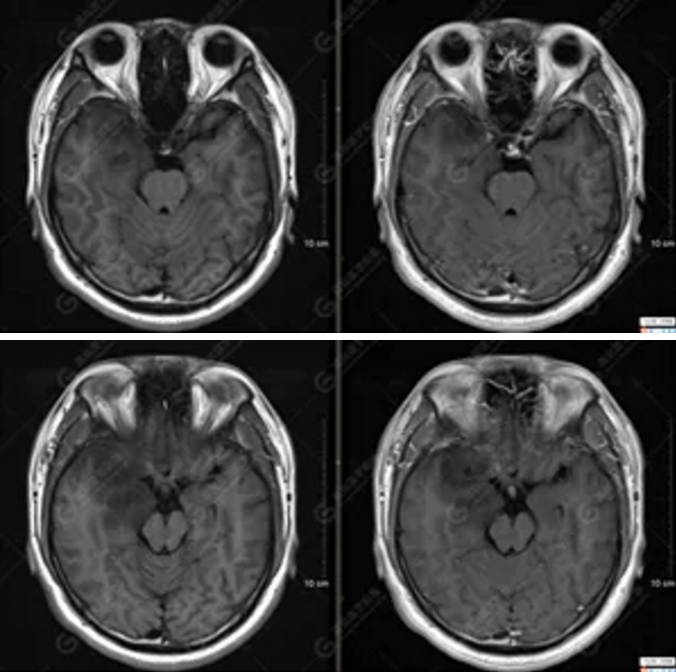

以上為DTI成像,圖1為皮質(zhì)脊髓束,圖2為胼胝體束,圖3為扣帶回束,圖4為額枕束。DTI成像示右側(cè)額枕束前部明顯受壓、部分未見(jiàn)顯示;胼胝體束、雙側(cè)扣帶束、皮質(zhì)脊髓束及左側(cè)額枕束形態(tài)可,纖維束未見(jiàn)明顯破壞,未見(jiàn)明顯稀疏減少。

1.右側(cè)額顳島葉、右側(cè)海馬及右側(cè)基底節(jié)區(qū)占位病變,考慮為彌漫性星形細(xì)胞瘤可能性大,累及右側(cè)大腦中動(dòng)脈、右側(cè)下丘腦及視交叉;

2.DTI成像示右側(cè)額枕束前部明顯受壓、部分未見(jiàn)顯示。